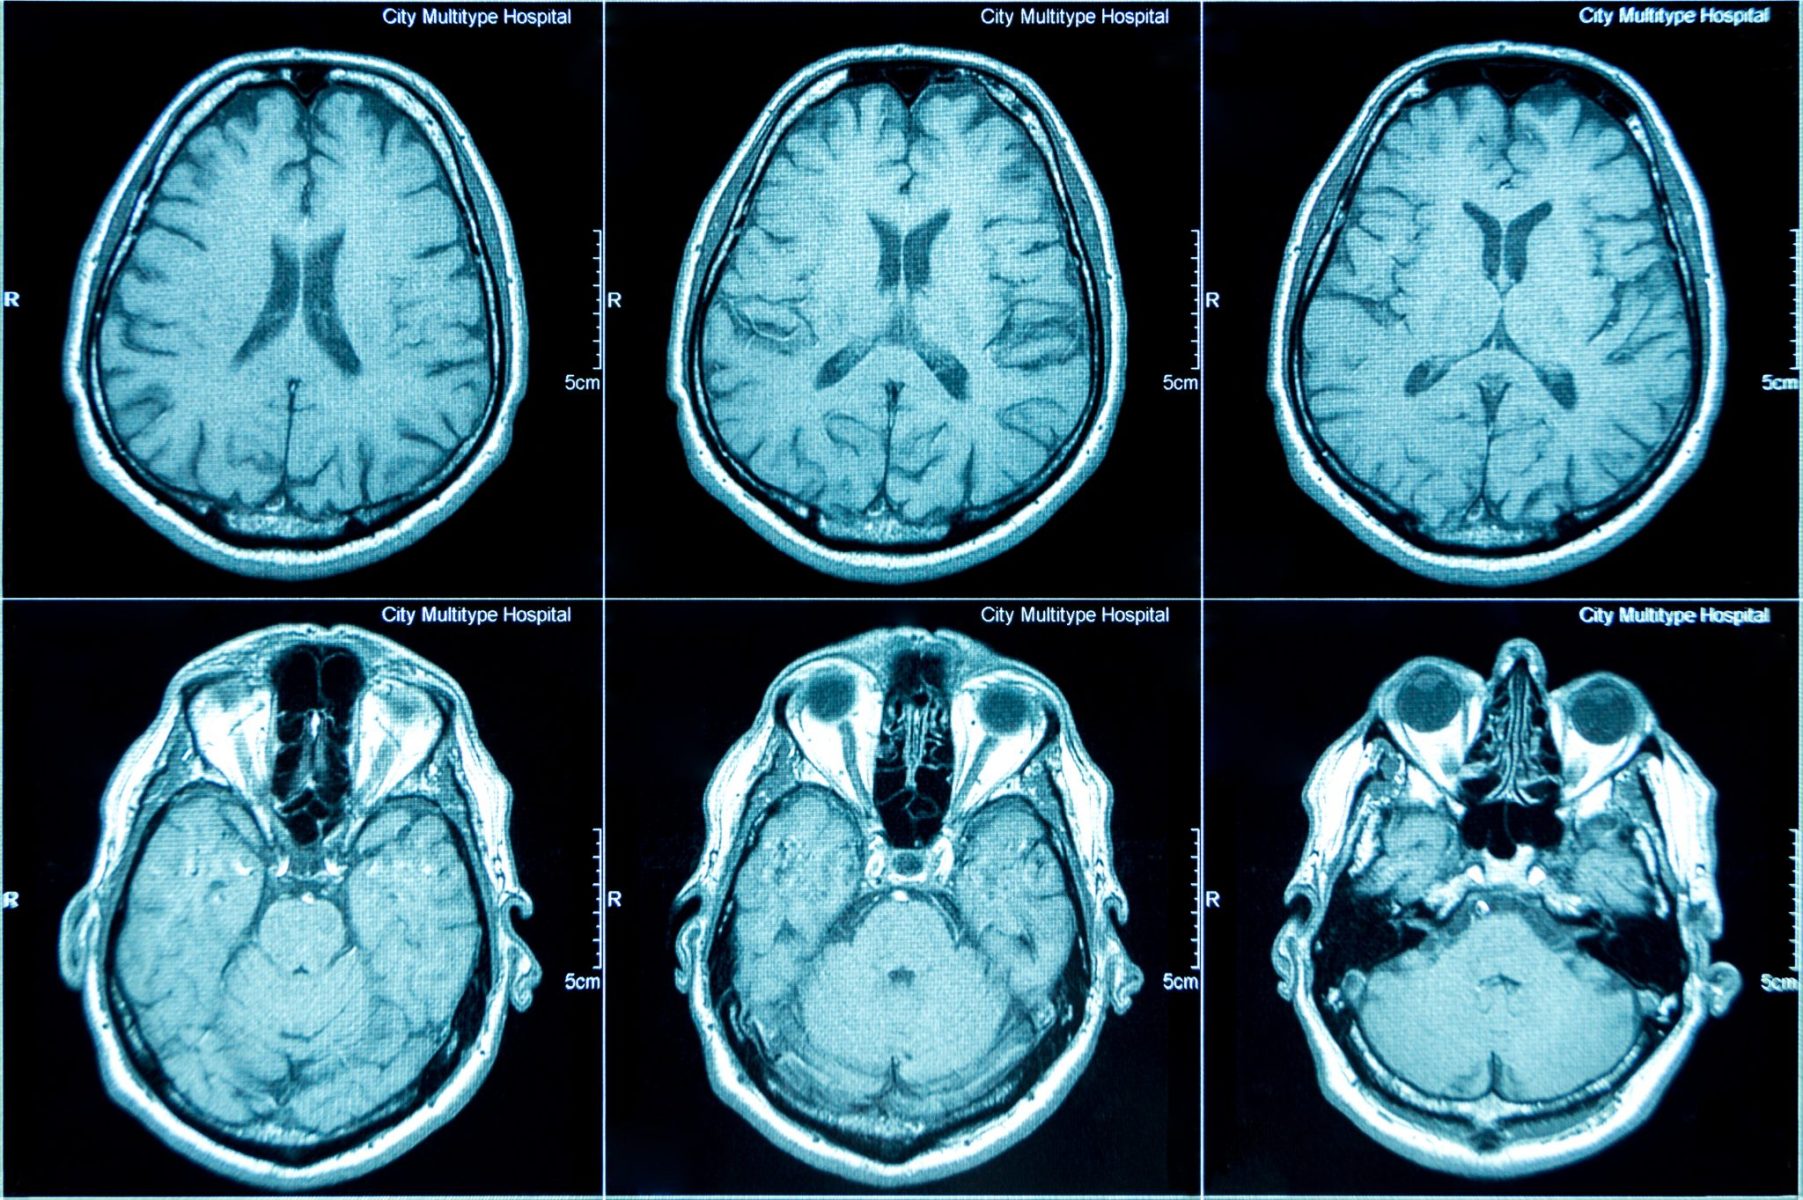

MRI scan image of brain Regional Medical Imaging Brain Mri After Car Accident headaches are common after a motor vehicle accident (mva). traumatic brain injury (tbi) refers to damage to the brain caused by an external physical force such as a car accident, a gunshot wound to. this review focuses on white matter (wm) changes in mild traumatic brain injury (mtbi) as assessed by multimodal. one of the most. Brain Mri After Car Accident.